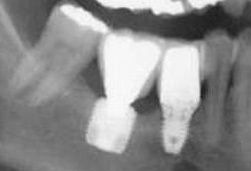

So stellt die Behandlung mittels kürzerer Implantate eine interessante Alternative zur aufwendigen, chirurgischen Therapie dar.

Die fortschreitende Weiterentwicklung des Implantatdesigns und der Implantatoberflächen bei gleichzeitiger Ursachenforschung für Implantatverluste öffnen die Möglichkeiten zur Anwendung mit kurzen Implantaten.

Neuere Untersuchungen zeigen, dass Überlebensraten mit kurzen Implantaten bis zu 95 % im Oberkiefer zwischen 88 und 100 % im Unterkiefer möglich sind.